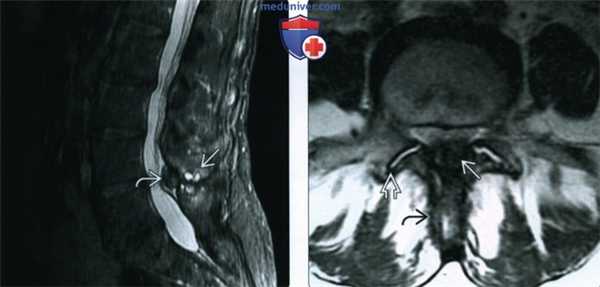

(Слева) МРТ, сагиттальная проекция, режим STIR: типичная межостистая дегенерация (болезнь Бострупа). Визуализируется кистозная дегенерация связки L4-L5 с округлыми зонами Т2 гиперинтенсивного сигнала в структуре гипертрофированной связки, характеризующейся сигналом низкой интенсивности.

(Справа) МРТ, аксиальная проекция, режим Т2: дегенеративные изменения сопряженных кортикальных краев заднего отдела остистого отростка у этого же пациента. Избыточная желтая связка и гипертрофия дугоотростчатых суставов способствуют развитию стеноза позвоночного канала.